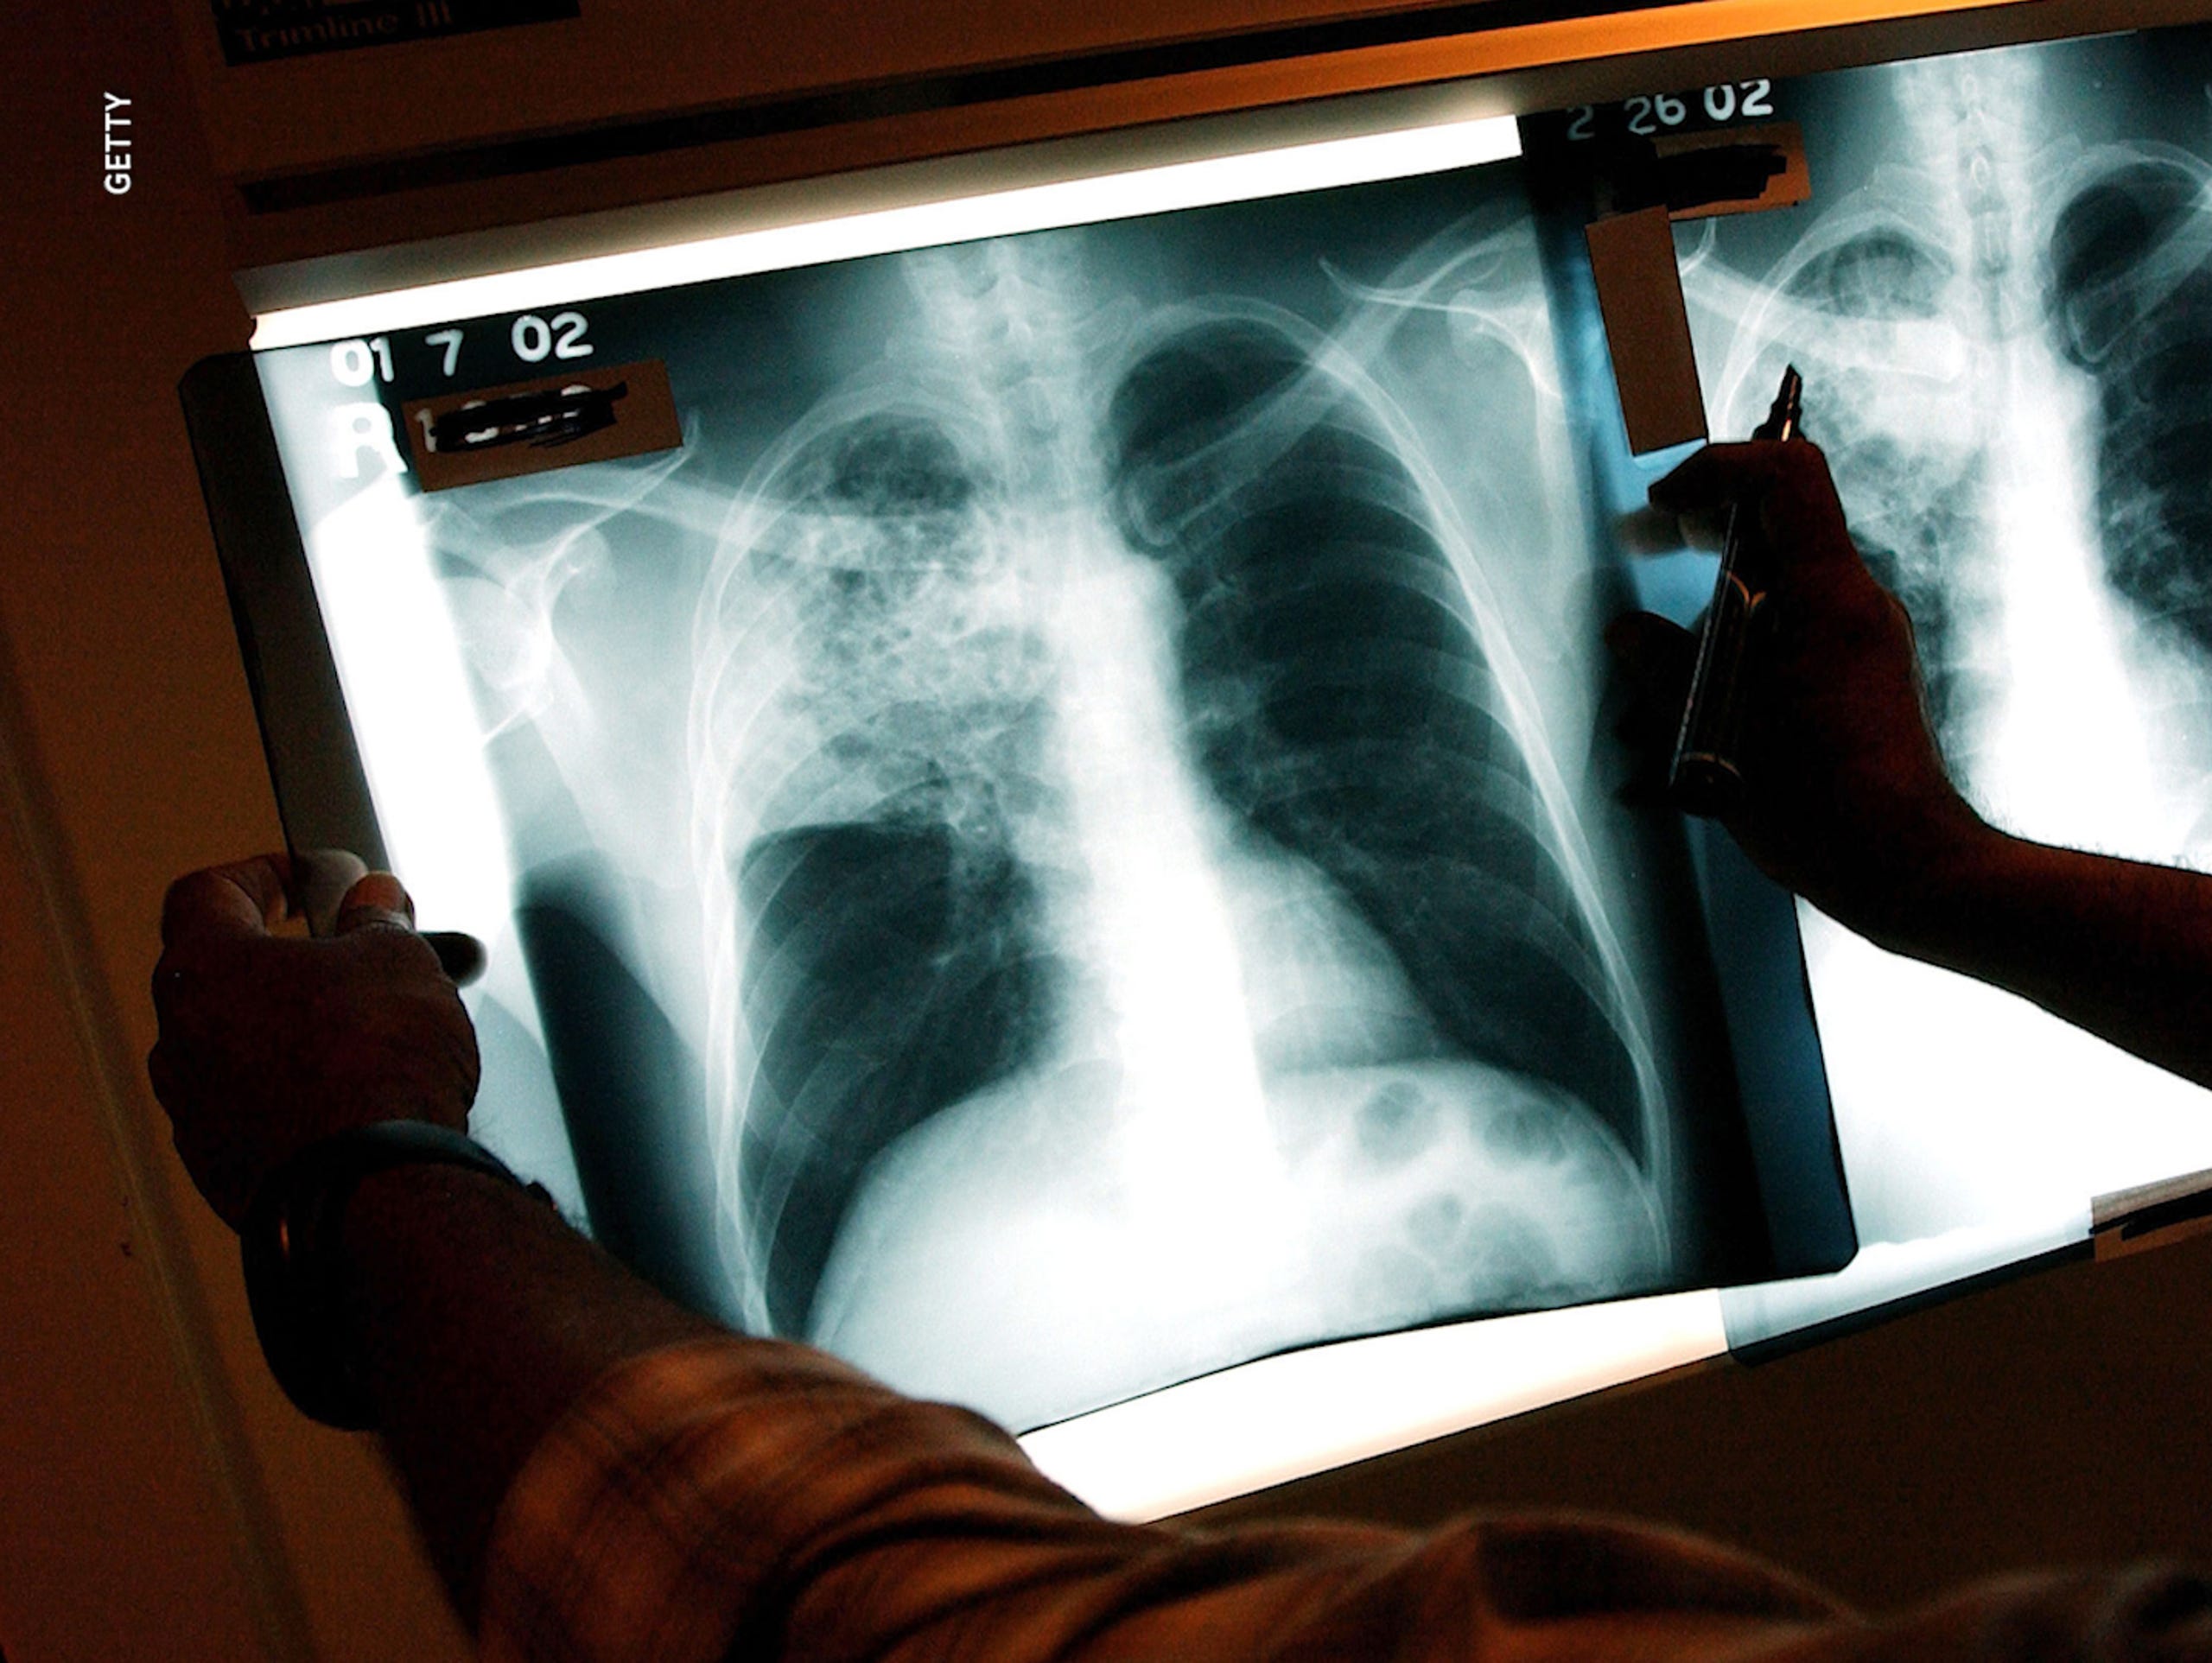

Tuberculosis and COVID-19 may both be respiratory diseases, but there are differences.

A bacteria causes tuberculosis; a virus genetically related to the severe acute respiratory syndrome coronavirus, SARS-CoV, causes COVID-19. Both are spread through close physical contact. When a tuberculosis-infected individual coughs, Mycobacterium tuberculosis can remain suspended in the air longer, until it’s inhaled by someone else, usually in a confined space.

“(Tuberculosis) basically puts a little ‘bunker’ inside your lung and hangs out there until you have a weakness in the immune system,” Sinha said. “Say you get HIV, start steroids or cancer therapy. In those weak moments, the bacteria emerges from the ‘bunker’ and infects the rest of your lungs.”

Once activated, tuberculosis does not stay in the lungs: It can infect the central nervous system (which includes the brain), muscles, skin, liver, lymph nodes and reproductive organs. Tuberculosis can persist in the body for up to 30 years, Ahuja said.